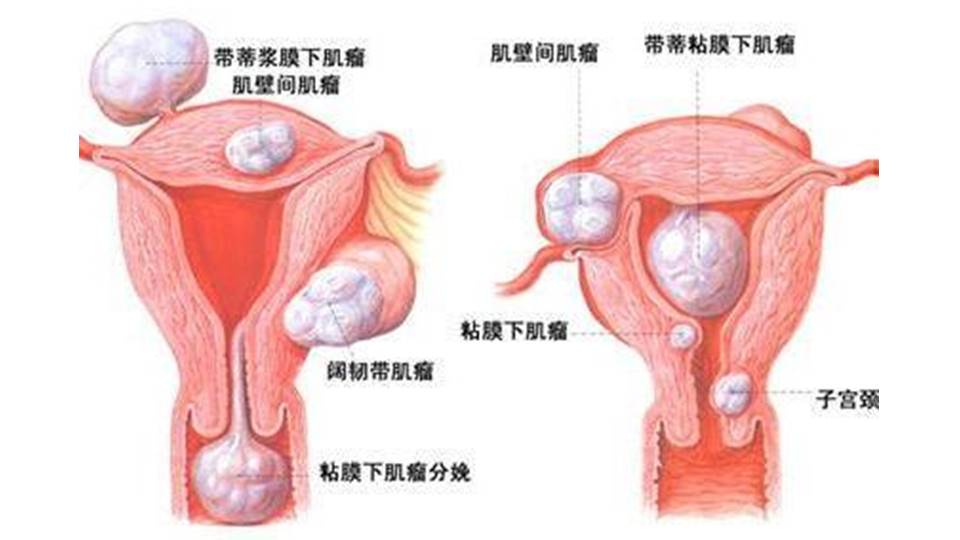

子宫肌瘤:

好发于30~50岁约占绝经期前妇女的70%~80%肌瘤常为多发,大小不等。发生部位以子宫体最多见。病理表现:子宫肌瘤主要由旋涡状排列的平滑肌细胞构成。肌瘤外表有一层结缔组织束和纤维构成的假性包膜。较大肌瘤由于血供障碍可发生多种变性,包括玻璃样变性、黏液样变性、脂肪样变性等,也可发生坏死、囊变、出血,子宫肌瘤恶变的概率很低,不足1%。

不典型肌瘤:退变型:玻璃样变 (>60%),囊变 (~4%),黏液样变,红色样变,水肿不是退变的表现(50%),出血、坏死和钙化 (~4%)。不典型生长部位:腹膜后(阔韧带)、寄生型、宫颈。特殊类型:脂肪平滑肌瘤,黏液性平滑肌瘤,浆膜下子宫肌瘤。